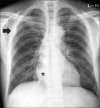

Immunoglobulin G4 (IgG4)-related disease is a newly recognized condition characterized by fibroinflammatory lesions with dense lymphoplasmacytic infiltration, storiform-type fibrosis and obliterative phlebitis. The pathogenesis is not fully understood but multiple immune-mediated mechanisms are believed to contribute. This rare disease can involve various organs and pleural involvement is even rarer. We report a case of IgG4-related disease involving pleura. A 66-year-old man presented with cough and sputum production for a week. Chest radiography revealed consolidation and a pleural mass at right hemithorax. Treatment with antibiotics resolved the consolidation and respiratory symptoms disappeared, but the pleural mass was unchanged. Video-assisted thoracoscopic surgery was performed. Histopathology revealed dense lymphoplasmacytic infiltration and storiform fibrosis with numerous IgG4-bearing plasma cells. The serum IgG4 level was also elevated. Further examination ruled out the involvement of any other organ. The patient was discharged without further treatment and there is no evidence of recurrence to date.